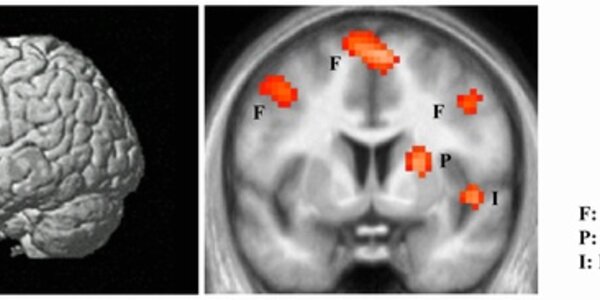

Brain's 'Hate Circuit' Identified

People who view pictures of someone they hate display activity in distinct areas of the brain that, together, may be thought of as a ‘hate circuit’, according to new research by scientists at University College London. The study, by Professor Semir Zeki and John Romaya of the Wellcome Laboratory of Neurobiology at UCL, examined the brain areas that correlate with the sentiment of hate and shows that the ‘hate circuit’ is distinct from those related to emotions such as fear, threat and danger – although it shares a part of the brain associated with aggression. The circuit is also quite…